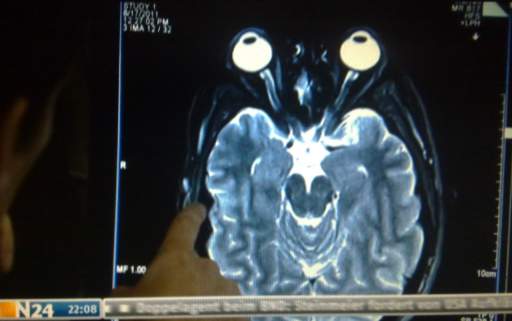

was diese fMRT experimente angeht ?

ES WIRD VERSUHT DIE METHODEN DIE ZUM MESSEN DES ERFOLGES UND DER REICHWEITE VON WERBUNG ANZUWENDEN AUF PROPAGANDA GANZ ALLGEIMEIN! (inwieweit wird das verhlaten des einzelnen von der anderen beeinflußt - siehe ?DIE WELLE? - auch ?TRITTBERETTFAHRER EFFEKT? (vom Phänomen des auf einen fahrenden Zug aufspringens) steht überall falsch)

Was hat jetzt aber John Lennon mit fMRT Experimenten zu zun (abgeshen von Chapmans Shculdunfähigkeit)? Wir erinenrn usn dan die Mehtoden - jeamnd wird Stressoren ausgestzt (?MEIN FERNSHEER LÜGT?) beispielsweise durch ein frensehprogramm was nur für ihn ausgetrahlt wird

Würde man nurn mit einer fMRT ähnlichen Methode verwuchen im weitesten Sinne Gednaken zu lesen wäre eine UNBEMERKT Studie am besten dadruch zu verifizieren daß man die Kommunikation der Kotrollgruoppe - mittesl FACEBOOK beispielsweise abhört.

?ich bin der meinung aus der mimik von jemandem herausgelesen zu haben er will eine cola trinken - ich zeige ihm einen spot - und lese an seienr reaktion bei dfacebook ab ob das ein so wesentlicher anreiz war dass er sch die müe amcht aufzuschreiben -> ?als hätte ich gerade daran gedacht?? das ist genau das system welches im link ganz oben mit dr fMRT angewendet wird.